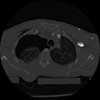

22 ANGIO,CE,Vol,0.5,ANGIO,,